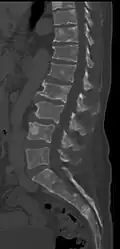

The diagnostic examination of a person with suspected multiple myeloma typically includes a skeletal survey. This is a series of X-rays of the skull, axial skeleton, and proximal long bones. Myeloma activity sometimes appears as "lytic lesions" (with local disappearance of normal bone due to resorption) or as "punched-out lesions" on the skull X-ray ("raindrop skull"). Lesions may also be sclerotic, which is seen as radiodense.[76] Overall, the radiodensity of myeloma is between −30 and 120 Hounsfield units (HU).[77] Magnetic resonance imaging is more sensitive than simple X-rays in the detection of lytic lesions. An MRI may supersede a skeletal survey, especially when vertebral disease is suspected. Occasionally, a CT scan is performed to measure the size of soft-tissue plasmacytomas. Nuclear Medicine Bone scans are typically not of any additional value in the workup of people with myeloma (no new bone formation; lytic lesions not well visualized on nuclear bone scan).

Pathological fracture of the lumbar spine due to multiple myeloma

Pathological fracture of the lumbar spine due to multiple myeloma -

CT scan of the lower vertebral column in a man with multiple myeloma, showing multiple osteoblastic lesions: These are more radiodense (brighter in this image) than the surrounding cancellous bone, in contrast to osteolytic lesions, which are less radiodense.

CT scan of the lower vertebral column in a man with multiple myeloma, showing multiple osteoblastic lesions: These are more radiodense (brighter in this image) than the surrounding cancellous bone, in contrast to osteolytic lesions, which are less radiodense. -